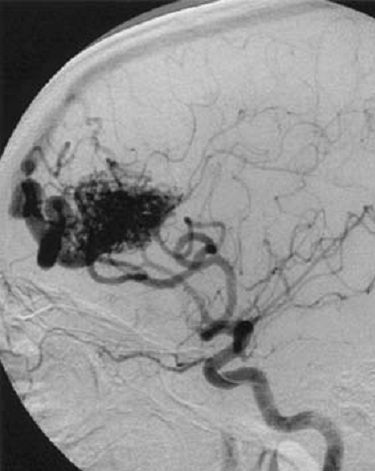

лизация мальформации

Эмболизация мальформации 113 фотографий